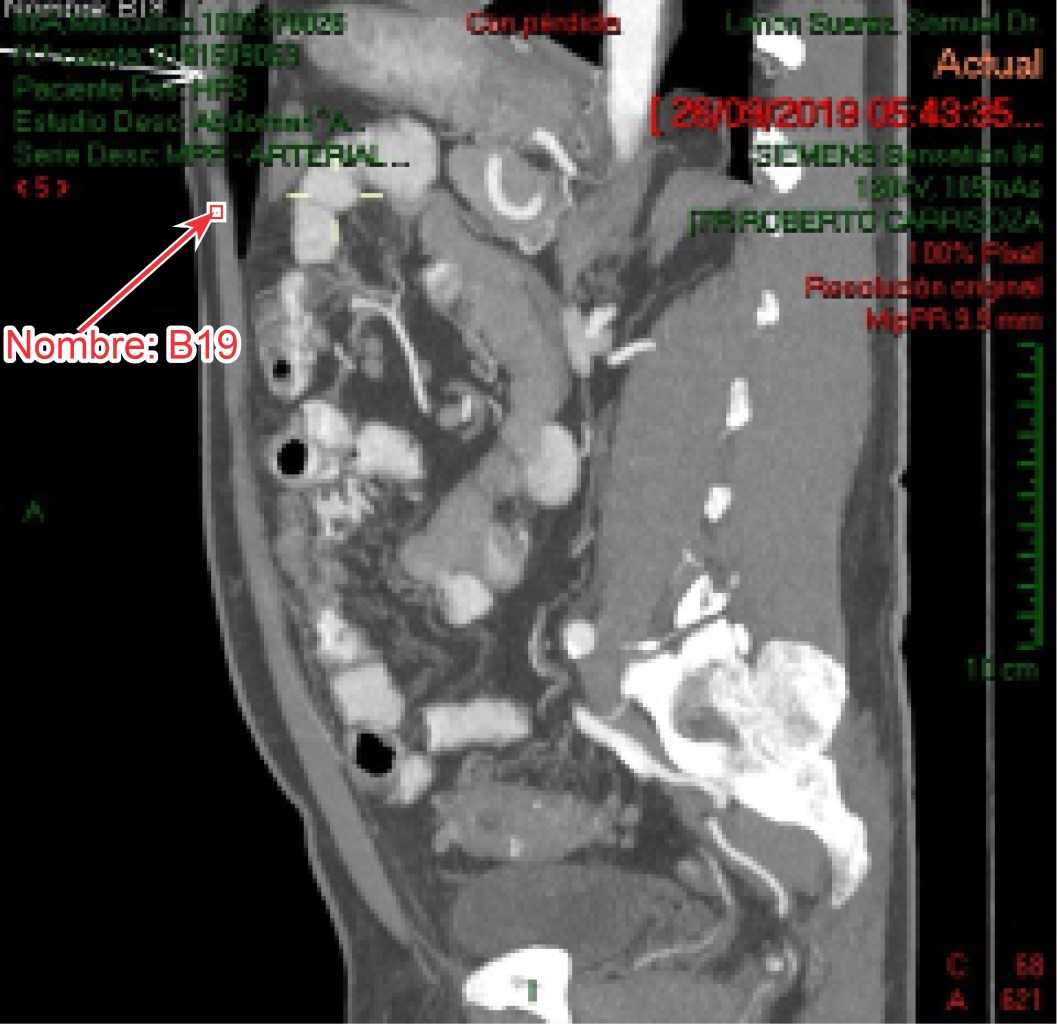

Jejunal diverticulitis with asymptomatic pneumoperitoneum. Non-operative management considerations

Introduction: Jejunal diverticula are saculations located on the mesenteric edge of the jejunum whose incidence is 0.2 to 4%. Pneumoperitoneum frequently translates acute surgical abdomen but can occur in pathologies that do not require surgical exploration. Objective: To recognize this pathology as an infrequent cause of chronic abdominal pain or acute surgical abdomen. Establish recommendations for its management. Clinical case: 66 years old male with intense colic, postprandial, nocturnal abdominal pain with severe abdominal distension, meteorism, persistent nausea, chronic diarrhea and early satiety with loss of appetite. Abdomen painful, tympanic, peristalsis greatly increased without data of peritoneal irritation. APP: systemic arterial hypertension controlled with ARA-2. A CT scan of the abdomen is performed with a report of jejunal diverticulitis and open air in the abdominal cavity. Conclusion: Jejunal diverticulitis, infrequent pathology, is susceptible to conservative medical treatment as long as the patient's conditions allow; in cases of complications, surgical treatment with resection and intestinal anastomosis is the recommended approach.

Figure 1